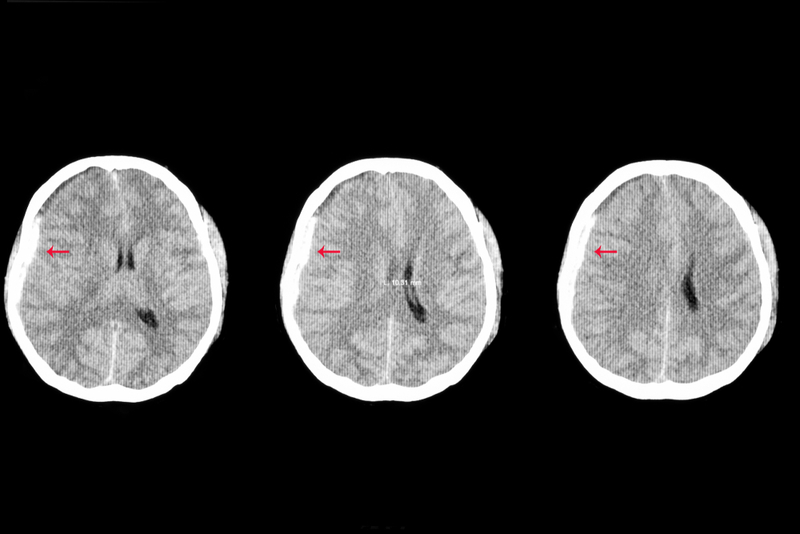

Researchers have identified a new mechanism that may contribute to Alzheimer's disease and traumatic brain injury, hoping that the discovery may lead to effective treatment.

In the cases of Alzheimer's and traumatic brain injury, the build-up of KCNB1 is associated with severe damage of mental function. As a result of this discovery, the researcher successfully tested a drug called Sprycel in mice. The drug is used to treat patients with leukemia. The research team now hopes to launch a clinical trial to test the treatment in humans.